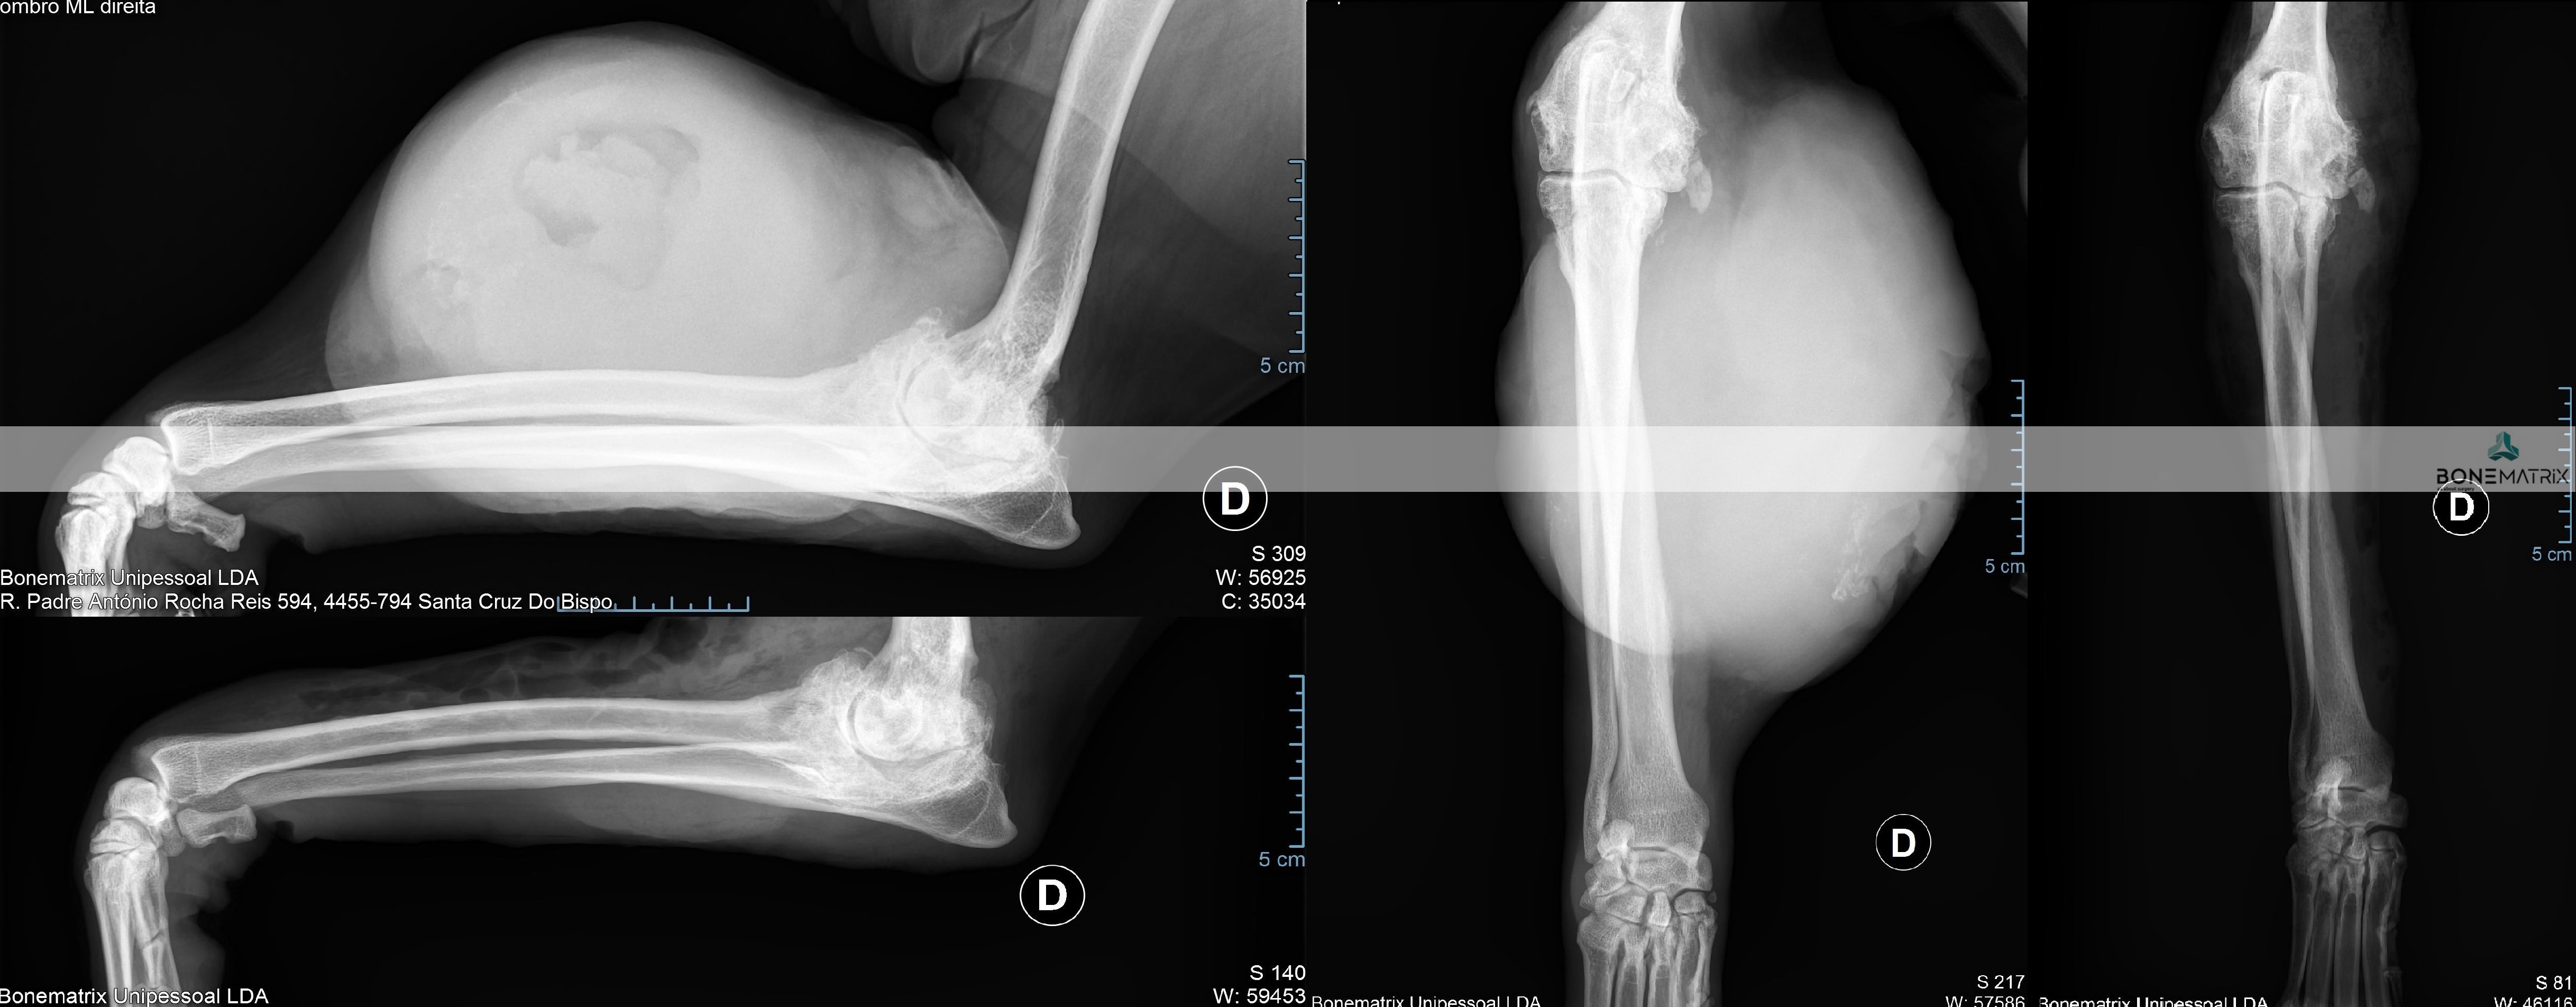

A displasia de cotovelo é uma doença de desenvolvimento caracterizada pela incongruência do cotovelo.

Dada a componente genética, frequentemente envolvida no decorrer deste processo, a patologia apresenta-se por norma bilateralmente, podendo assumir gravidade diferente em ambos os cotovelos.

A displasia de cotovelo pode assumir várias apresentações, entre elas, a não união do processo ancóneo, a fragmentação do processo coronóide, a osteocondrite dissecante, doença do compartimento medial e a incongruência per si.

A articulação do cotovelo é constituída por 3 ossos, o rádio, a ulna e o úmero.

A incongruência do rádio resulta na apresentação deste osso mais curto que a ulna. Isto resulta num excesso de pressão sobre regiões da ulna - resulta com frequência na fragmentação do processo coronóide.

Quando a apresentação contrária ocorre, ou seja, o rádio apresenta-se mais elevado que a ulna, é exercida demasiada pressão sobre o processo ancóneo - resultando com frequência na não união do processo ancóneo.

Quando a incongruência envolve o úmero outras lesões podem ser desenvolvidas que envolvem o desalinhamento articular entre o úmero e a ulna.

Os cães com predisposição para a apresentação desta patologia são os cães de crescimento rápido, ou seja, cães de raça grande a gigante, onde existe com frequência problemas no crescimento harmonioso destes ossos.

O diagnóstico pode ser realizado por meio de estudo radiográfico.

Contudo são indicadas técnicas de imagem avançada (tomografia axial computorizada) ou artroscopia para a realização do diagnóstico final e definição de abordagem terapêutica.

O que é?

A osteocondrite dissecante é uma condição que surge durante o crescimento devido a um distúrbio na diferenciação das células de cartilagem, o que resulta numa falha na ossificação endocondral (processo fundamental do desenvolvimento esquelético do feto e do cachorro em crescimento). Este defeito no crescimento resulta no aparecimento de um defeito ósseo tipicamente apresentado na cabeça do úmero, da qual se destaca um “flap” de cartilagem.

A genética é o fator de maior peso no aparecimento da OCD no ombro, bem como noutras articulações. Existem várias raças especialmente predispostas onde esta doença é mais comum, nomeadamente as de porte médio e grande. Algumas das raças mais afetadas são o Golden Retriever, Pastor Alemão, Bouvier de Berna, Rotweiller, Dogue Alemão, São Bernando, entre outras raças grandes a gigantes, embora com alguma frequência surja em Border Collie, Husky, Chow Chow ou outros cães de porte médio.

Como é feito o diagnóstico de OCD?

A suspeita surge quando se deteta claudicação, dor e desconforto no ombro, entre os 6 e 10 meses de idade. Alguns pacientes podem passar assintomáticos durante os primeiros anos, e mostrar desconforto numa fase mais avançada da doença e da idade. Após exame ortopédico, o diagnóstico é geralmente confirmado com um estudo radiográfico.

Situações mais subtis podem carecer de confirmação com estudo de TAC ou artrografia (radiografia com contraste articular).